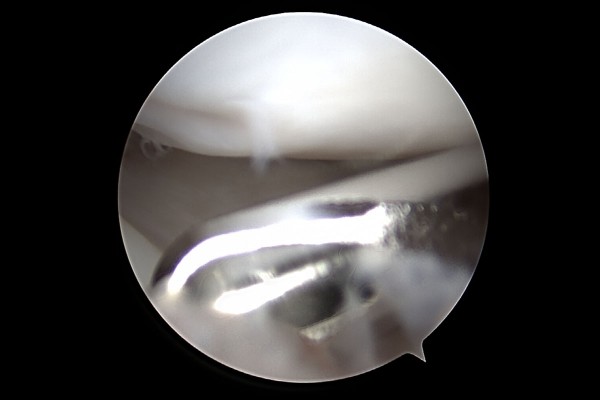

삼각섬유연골이 찢어진 부분이 확인되어

e2dae621a1572a5ea8be78c4dc6d0de9_1768291813_4109.jpg

주변부를 다듬어 준 뒤 레이저 기구를 이용하여 열 수축 처리하며 수술을 마무리 합니다.